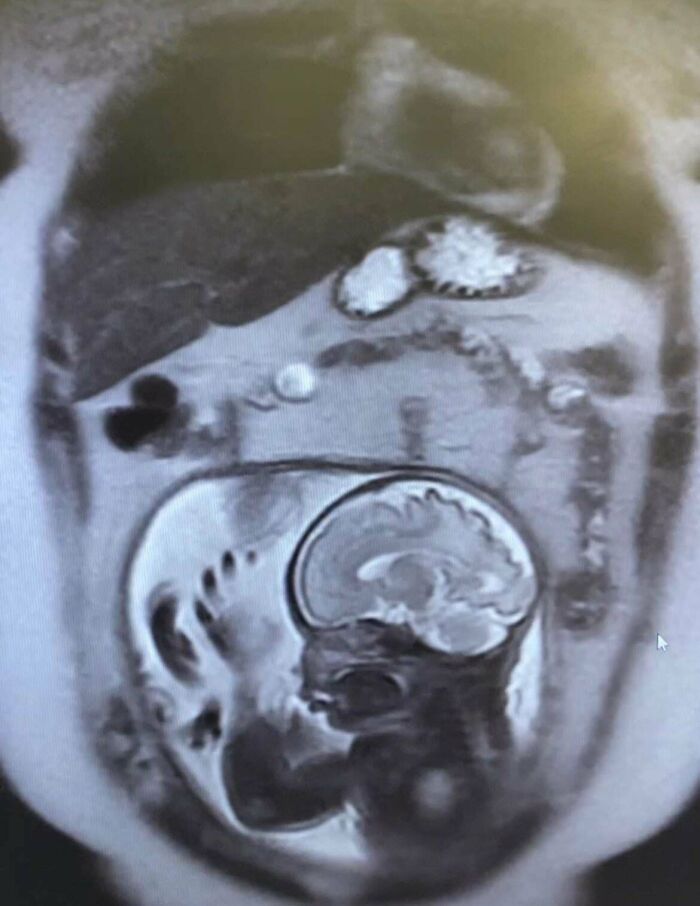

#50 An MRI View You Won’t See Everyday

Image credits: atgctgttt